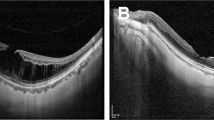

Fifty eyes of from 8 men and 39 women (mean age: 61.0 ± 7.5 years) were enrolled. The mean axial length was 29.42 ± 2.13 mm. The median follow-up time before and after LMH formation was 35 months (range: 5–90 months) and 47 months (range: 13–94 months), respectively. Four types of LMH formation processes were identified, including (1) type 1, LMH developed after foveal avulsion induced by VMT (8 cases) (Fig. 1a, b); (2) type 2, LMH developed after the inner medial wall of a parafoveal cyst or retinoschisis ruptured (32 cases) (Fig. 1c, d); (3) type 3, the ruptured central foveal cysts induced by ERM led to LMH formation (5 cases) (Fig. 1e, f); and (4) type 4, progressive foveal thinning was induced by an ERM, and the LMH formed without an intervening stage of cyst or retinoschisis (5 cases) (Fig. 1g, h). Table 1 shows the clinical characteristics of LMH with different formation processes. Type 2 LMH was the most common (64%). Type 4 LMH had the highest rate (80%) of ellipsoid zone disruption, but no EP. Sixty percent of type 3 LMHs were A-shaped, while V-shaped LMH was the predominant form in other types. In some patients, the LMH initially resembled a “tractional type” LMH and evolved into a “degenerative type” configuration later (Fig. 1i-l). Table 2 shows the changes in the clinical characteristics of LMH during the follow-up. The BCVA of patients with type 2 (P = 0.003, paired Wilcoxon rank-sum test) and type 4 LMHs (P = 0.029, paired Wilcoxon rank-sum test) decreased significantly during follow-up. Among all types, patients with type 4 LMH had the most significant decline (1.03 ± 0.69) of visual acuity (P = 0.024, Kruskal-Wallis test). The vertical depth of type 2 (P = 0.041, paired Wilcoxon rank-sum test) and type 4 (P = 0.017) LMHs increased significantly. The type 4 LMHs had the more significant increase in vertical depth than the type 3 LMHs (P = 0.032, post-hoc analysis of Kruskal-Wallis test). A significant widening of the LMH was seen in type 3 LMHs (P = 0.001, paired Wilcoxon rank-sum test). The RFT of type 2 (P = 0.040, paired Wilcoxon rank-sum test) and type 4 LMHs (P = 0.024) decreased significantly. The type 4 LMHs had the more significant decrease in RFT than the type 1 LMHs (P = 0.015, post-hoc analysis of Kruskal-Wallis test).

a–h Four types of developmental processes of LMH (a, b) Type 1 LMH develops after the avulsion of foveal tissue induced by vitreomacular traction (c, d) Type 2 LMH develops after the disruption of the medial wall of the parafoveal cyst (e, f) Type 3 LMH develops after the deroofing of the central foveal cyst (g, h) Type 4 LMH develops from the progressive central foveal thinning induced by the epiretinal membrane. Intraretinal cyst or schisis is not observed. i–l A representative case of LMH evolved from the “tractional configuration” into “degenerative configuration”. i, j LMH develops from the disruption of the foveal cyst by vitreomacular traction (type 1). k It has the features of “tractional LMH” with foveoschisis and a sharp edge. l Four years later, it has transformed into a “degenerative LMH” with a foveal bump and a round edge (asterisk). m–r The different chronological sequences of the LMH and macular retinoschisis (m, n) Group 1: LMH formed before the development of retinoschisis (o, p) Group 2: LMH and retinoschisis developed concurrently (q, r) Group 3: LMH developed in the presence of retinoschisis.

We found that LMHs had distinct evolutions and outcomes according to the different developmental processes, and our classification might have some clinical relevance. Patients with the most common type 2 LMH had ERM with foveoschisis or myopic retinoschisis as a pre-LMH condition. Subsequently, the medial walls of parafoveal cysts ruptured and transformed into LMHs. When combined with macular retinoschisis, LMHs deepened, and the RFT decreased during follow-up, accompanied by visual deterioration. Half of the patients experienced anatomical worsening or progression. Type 3 LMHs developed from the deroofing of foveal cysts induced by vitreous traction or ERM. Subsequently, foveoschisis between the outer plexiform layer and the outer nuclear layer might have occurred, and the horizontal width of LMHs increased significantly. Therefore, type 3 LMHs often acquired an A-shaped configuration, which was protective against progression [14]. We postulated the wider base of A-shaped LMH could dissipate the traction force, thus visual function was more likely to be preserved in this type. Type 1 LMH formed by avulsion of the foveal tissue owing to VMT, which was regarded as the abortive form of full-thickness MH. The width of LMHs and RFT remained stable since the traction had been released. In types 1–3 LMHs, avulsion of foveal tissue and disruption of cysts or schistic cavities were accompanied by the partial reduction of traction. In contrast, type 4 LMHs were induced by ERM without an intraretinal cyst stage. The persistent ERM traction acted directly on the fovea, and caused foveal thinning. Hence, the vertical depth of the LMH increased, and the residual foveal tissue became thinner. This type of LMH was prone to visual deterioration, and all progressed to full-thickness MHs.

The observation of the development and evolution of LMHs in HM eyes may have implications in the formation of idiopathic LMHs, of which the classification and definition have been revised several times [2, 3, 10]. Govetto et al. classified this macular lesion into “tractional LMH” and “degenerative LMH” [10]. Hubschman et al. further redefined the LMH-related lesions into “ERM with foveoschisis”, “LMH”, and “macular pseudohole”[3]. “ERM with foveoschisis” corresponds to the “tractional LMH”. The newly-defined “LMH”, comparable to the “degenerative LMH” has round-edged intraretinal cavitation affecting all retinal layers, and is associated with EP [10]. The classification implies the two different pathways of LMH development. However, recent studies have shown that tractional forces play a primary pathogenic role in degenerative LMHs [24, 25]. The VMT or ERM disrupts the Müller cells cone and induces outer retinoschisis. The damage of Henle fibres is followed by the degeneration of photoreceptors and the inner nuclear layer, which results in the formation of degenerative LMH [24]. In our cohort of HM eyes, the tractional forces could be identified in all cases. Different types of tractional forces, their points of exertion, and the net traction direction could lead to distinct formative and evolutionary processes. Clinical features of degenerative type LMH would develop later (Fig. 1i–l). Whether this observation could be applied to idiopathic conditions remains to be determined.